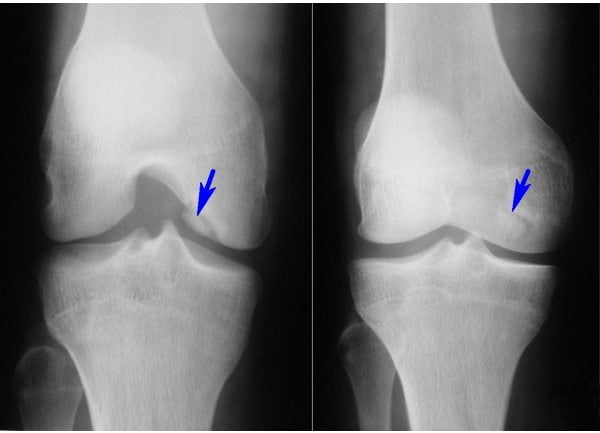

- рентгенография. Информативна при переломах костей, хронических артритах, остеоартрозе и т. д. Дает возможность выявить нарушение целостности или очаги деструкции в костях, формирующих коленный сустав;